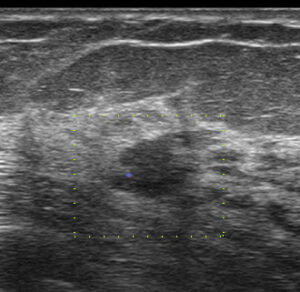

これが、当院受診時のエコー画像

やはり不整型 文句なしの「私cat.6」となります。